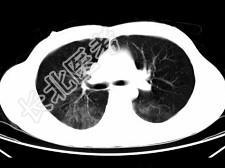

- 单项选择题男,35岁, 被车撞伤后1小时,结合影像图像选择其最可能的诊断为 ( )

D、肺挫伤